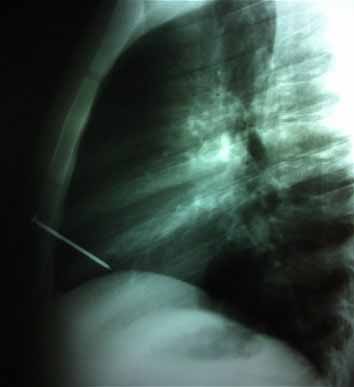

Szíven lőttek szöggel egy raklapgyártó férfit, de túlélte

Argentínában a 19 éves fiatalba 8 centi hosszú szög állt bele, amely átfúrta szívének egyik kamráját. A baleset a munkahelyén történt, egy fafeldolgozó üzemben, egyik kollégája véletlenül lőtte ki a szöget.

A sérülttel azonnal kórházba száguldottak, ahol kétórás műtéttel sikerült megmenteni az életét. A szöget egyszerűen ki is húzhatták volna a sérültből, ám attól tartottak az orvosok, hogy heves vérzés indíthatnak el, ráadásul még jobban megsérülhet a szívizom. Ezért felnyitották a férfi mellkasát, és rendkívül óvatosan távolították el az idegen testet.

Eddig összesen három ember élt túl hasonló balesetet a világon: egy az Egyesült Államokban, egy Ausztráliában, egy pedig Lengyelországban - emlékeztetett rá a The Daily Telegraph című brit lap.